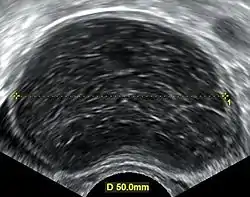

Transvaginal ultrasonography of a hemorrhagic ovarian cyst, probably originating from a corpus luteum cyst. The coagulating blood gives the content a cobweb-like appearance.

Ovarian cysts are usually diagnosed by ultrasound, CT scan, or MRI, and correlated with clinical presentation and endocrinologic tests as appropriate.

Ultrasound

Follow-up imaging in women of reproductive age for incidentally discovered simple cysts on ultrasound is not needed until 5 cm, as these are usually normal ovarian follicles. Simple cysts 5 to 7 cm in premenopausal females should be followed yearly. Simple cysts larger than 7 cm require further imaging with MRI or surgical assessment. Because they are large, they cannot be reliably assessed by ultrasound alone; it can be difficult to see posterior wall soft tissue nodularity or thickened septation due to limited ultrasound beam penetrance at this size and depth. For the corpus luteum, a dominant ovulating follicle that typically appears as a cyst with circumferentially thickened walls and crenulated inner margins, follow up is not needed if the cyst is less than 3 cm in diameter. In postmenopausal patients, any simple cyst greater than 1 cm but less than 7 cm needs yearly follow-up, while those greater than 7 cm need MRI or surgical evaluation, similar to reproductive age females.[9]